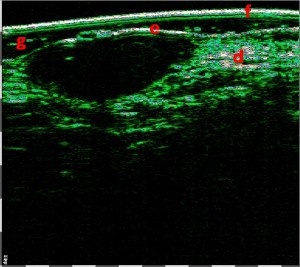

Σάρωση μελανώματος 75 MHz, υποανηχοϊκός όγκος

11 mm x 300 μm,

βάθος 140-190 μm από την επιφάνεια του δέρματος

ΔΕΙΚΤΗΣ BRESLOW – 0

(πάχος μελανώματος 0,28-0,3 mm)

ΕΠΙΠΕΔΟ CLARK – 2 (διείσδυση στο θηλώδες χόριο)

Η έγκαιρη ΜΗ ΕΠΕΜΒΑΤΙΚΗ αξιολόγηση της εξάπλωσης του όγκου (πάχος και επίπεδο διείσδυσης) πριν από τη θεραπεία έχει θεμελιώδη σημασία, καθώς επιτρέπει όχι μόνο τη διάγνωση, αλλά και την αποφυγή υπερδιάγνωσης. Η αξιολόγηση του μεγέθους και του σταδίου του όγκου με Υπέρηχο Υψηλής Συχνότητας – HFUS επιτρέπει την επιλογή της κατάλληλης χειρουργικής επέμβασης για την αφαίρεσή του, τον σχεδιασμό των πρόσθετων διαγνωστικών διαδικασιών για την αναζήτηση απομακρυσμένης μετάστασης, καθώς και τον σχεδιασμό της επικουρικής χημειοθεραπείας και ανοσοθεραπείας. Είναι σημαντικό, σε περίπτωση μελανώματος, ο υπερηχογράφος δέρματος υψηλής συχνότητας να επιτρέπει στον χειρουργό να σχεδιάζει τον όγκο της εκτομής ακριβώς σύμφωνα με τον δείκτη Breslow in vivo πριν από την επέμβαση.